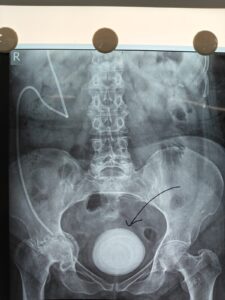

हरिद्वार, 28 अप्रैल। बहादराबाद स्थित जया मैक्सवेल हॉस्पिटल में डॉक्टरों की टीम ने एक बेहद जटिल सर्जरी को सफलतापूर्वक अंजाम देकर मरीज की जान बचाई। यूरोलॉजी विभाग के वरिष्ठ सर्जन डॉ. विपिन तिवानी के नेतृत्व में 14 सेंटीमीटर की विशाल मूत्राशय पथरी (ब्लैडर स्टोन) को ऑपरेशन के जरिए निकाला गया।

डॉक्टरों के अनुसार मरीज लंबे समय से पेशाब की धार कमजोर होने, तेज जलन, दर्द और रुक-रुक कर खून आने जैसी गंभीर समस्याओं से जूझ रहा था। जांच के दौरान मूत्राशय में 14 सेमी की बड़ी पथरी पाई गई, जिसने केस को और अधिक जटिल बना दिया।